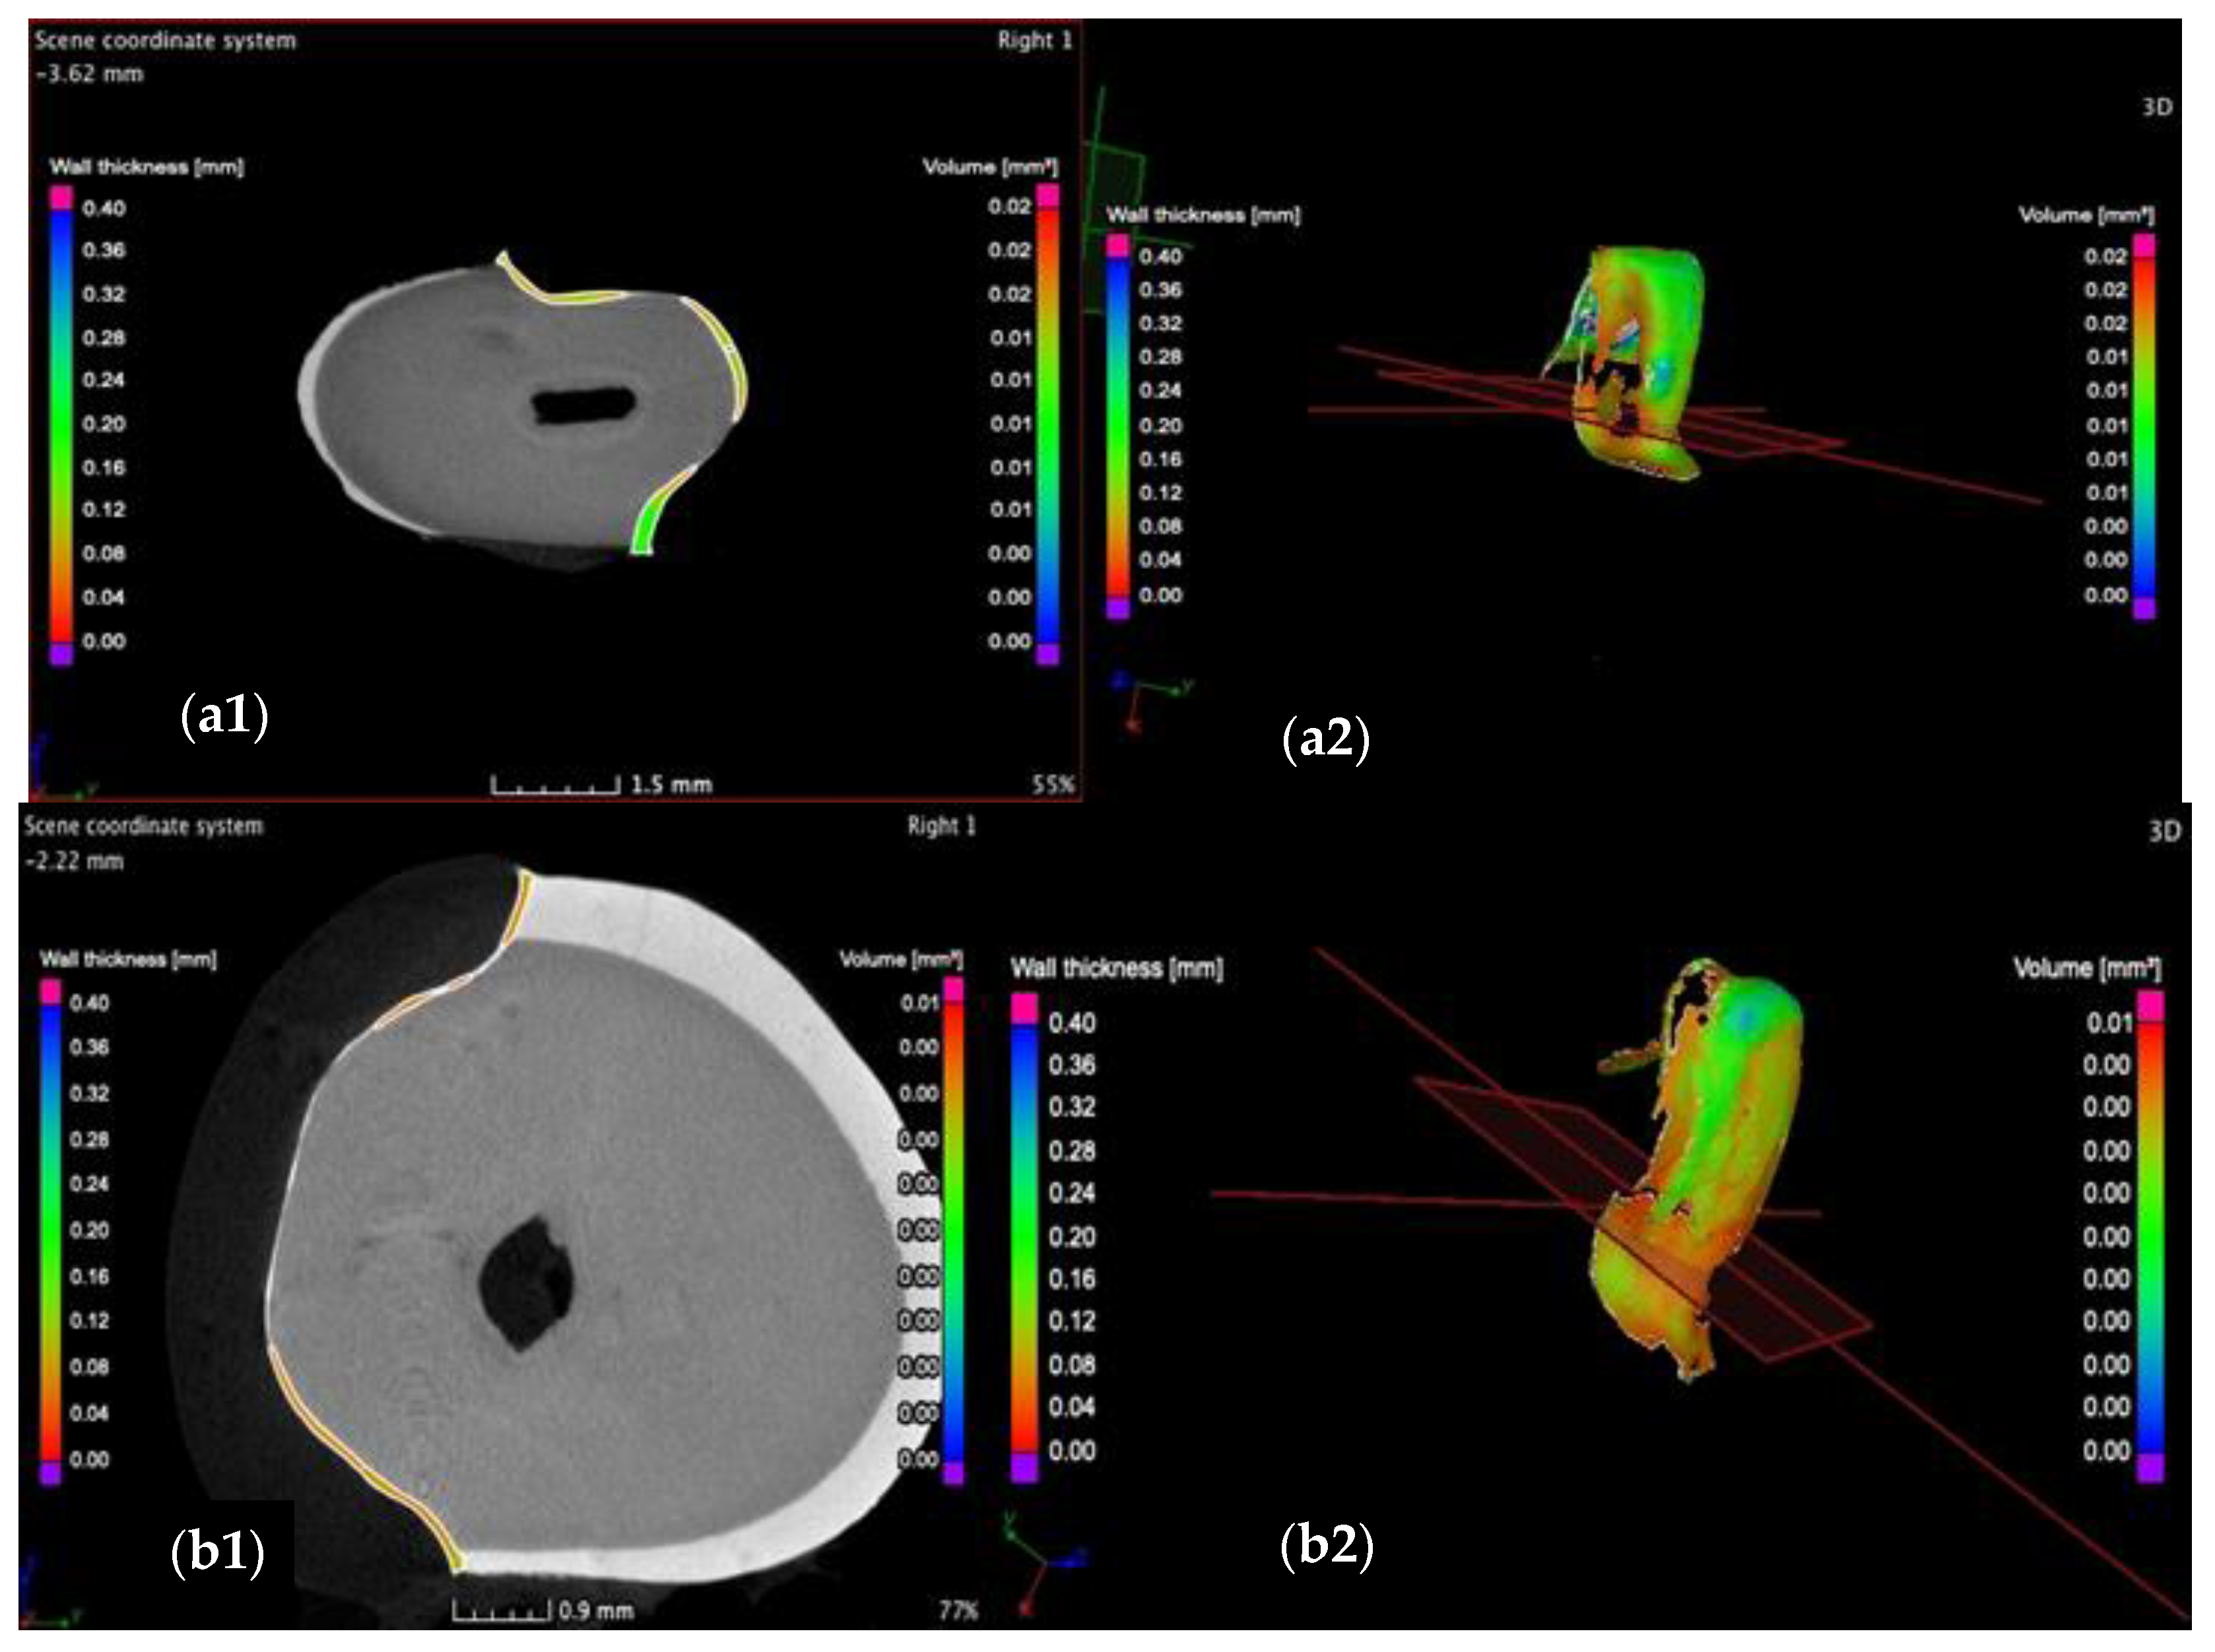

3.2. Micro-CT

3.3. Mathematical Modeling of the Micro-CT Results